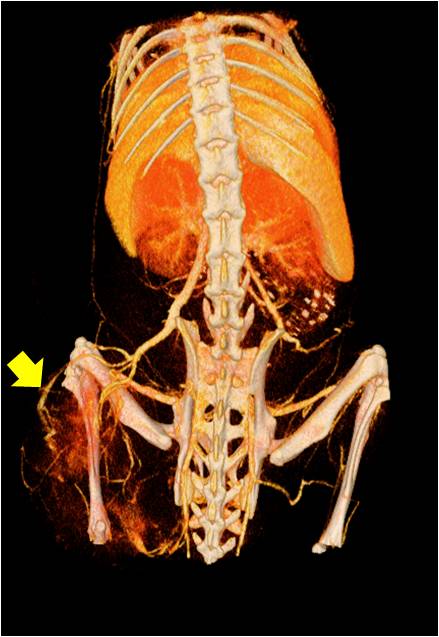

• 能進(jìn)行全身血管成像研究,獲得高分辨率的血管造影影像;

胸部和心血管的層析成像 胸部和心血管的3D圖像

心血管.jpg 心血管1.jpg